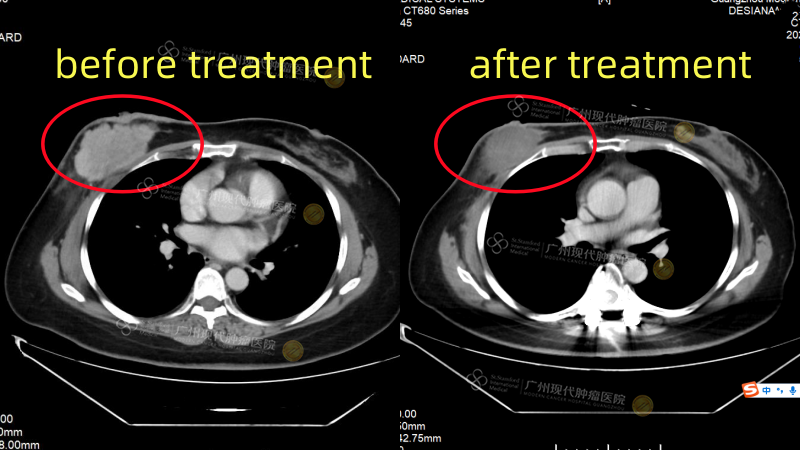

Seorang pasien kanker payudara asal Indonesia, Ny. Lin (nama samaran), yang ditangani oleh Prof. Dai, secara tak terduga mendapati adanya tumor payudara saat menjalani pemeriksaan kesehatan rutin. Saat diagnosis awal, penyakitnya telah menyebar ke kelenjar getah bening aksila dan tulang, bahkan menyebabkan penekanan pada sumsum tulang belakang, yang hampir membuatnya mengalami kelumpuhan. Setelah dilakukan diskusi dan evaluasi oleh tim MDT dari Modern Cancer Hospital Guangzhou, dirumuskan rencana pengobatan individual berupa “operasi tulang belakang yang dikombinasikan dengan terapi endokrin sistemik”. Sejak memulai pengobatan pada Agustus 2024 hingga saat ini, hasil evaluasi menunjukkan bahwa tumor dalam tubuh Ny. Lin telah mencapai status PR (Partial Response), yaitu penyusutan tumor lebih dari 50%. Kekuatan otot pada kedua tungkai bawahnya telah pulih sepenuhnya, kualitas hidupnya meningkat secara signifikan, dan ia berhasil terhindar dari risiko kelumpuhan.

Perbandingan CT Scan sebelum dan sesudah pengobatan Ny. Lin